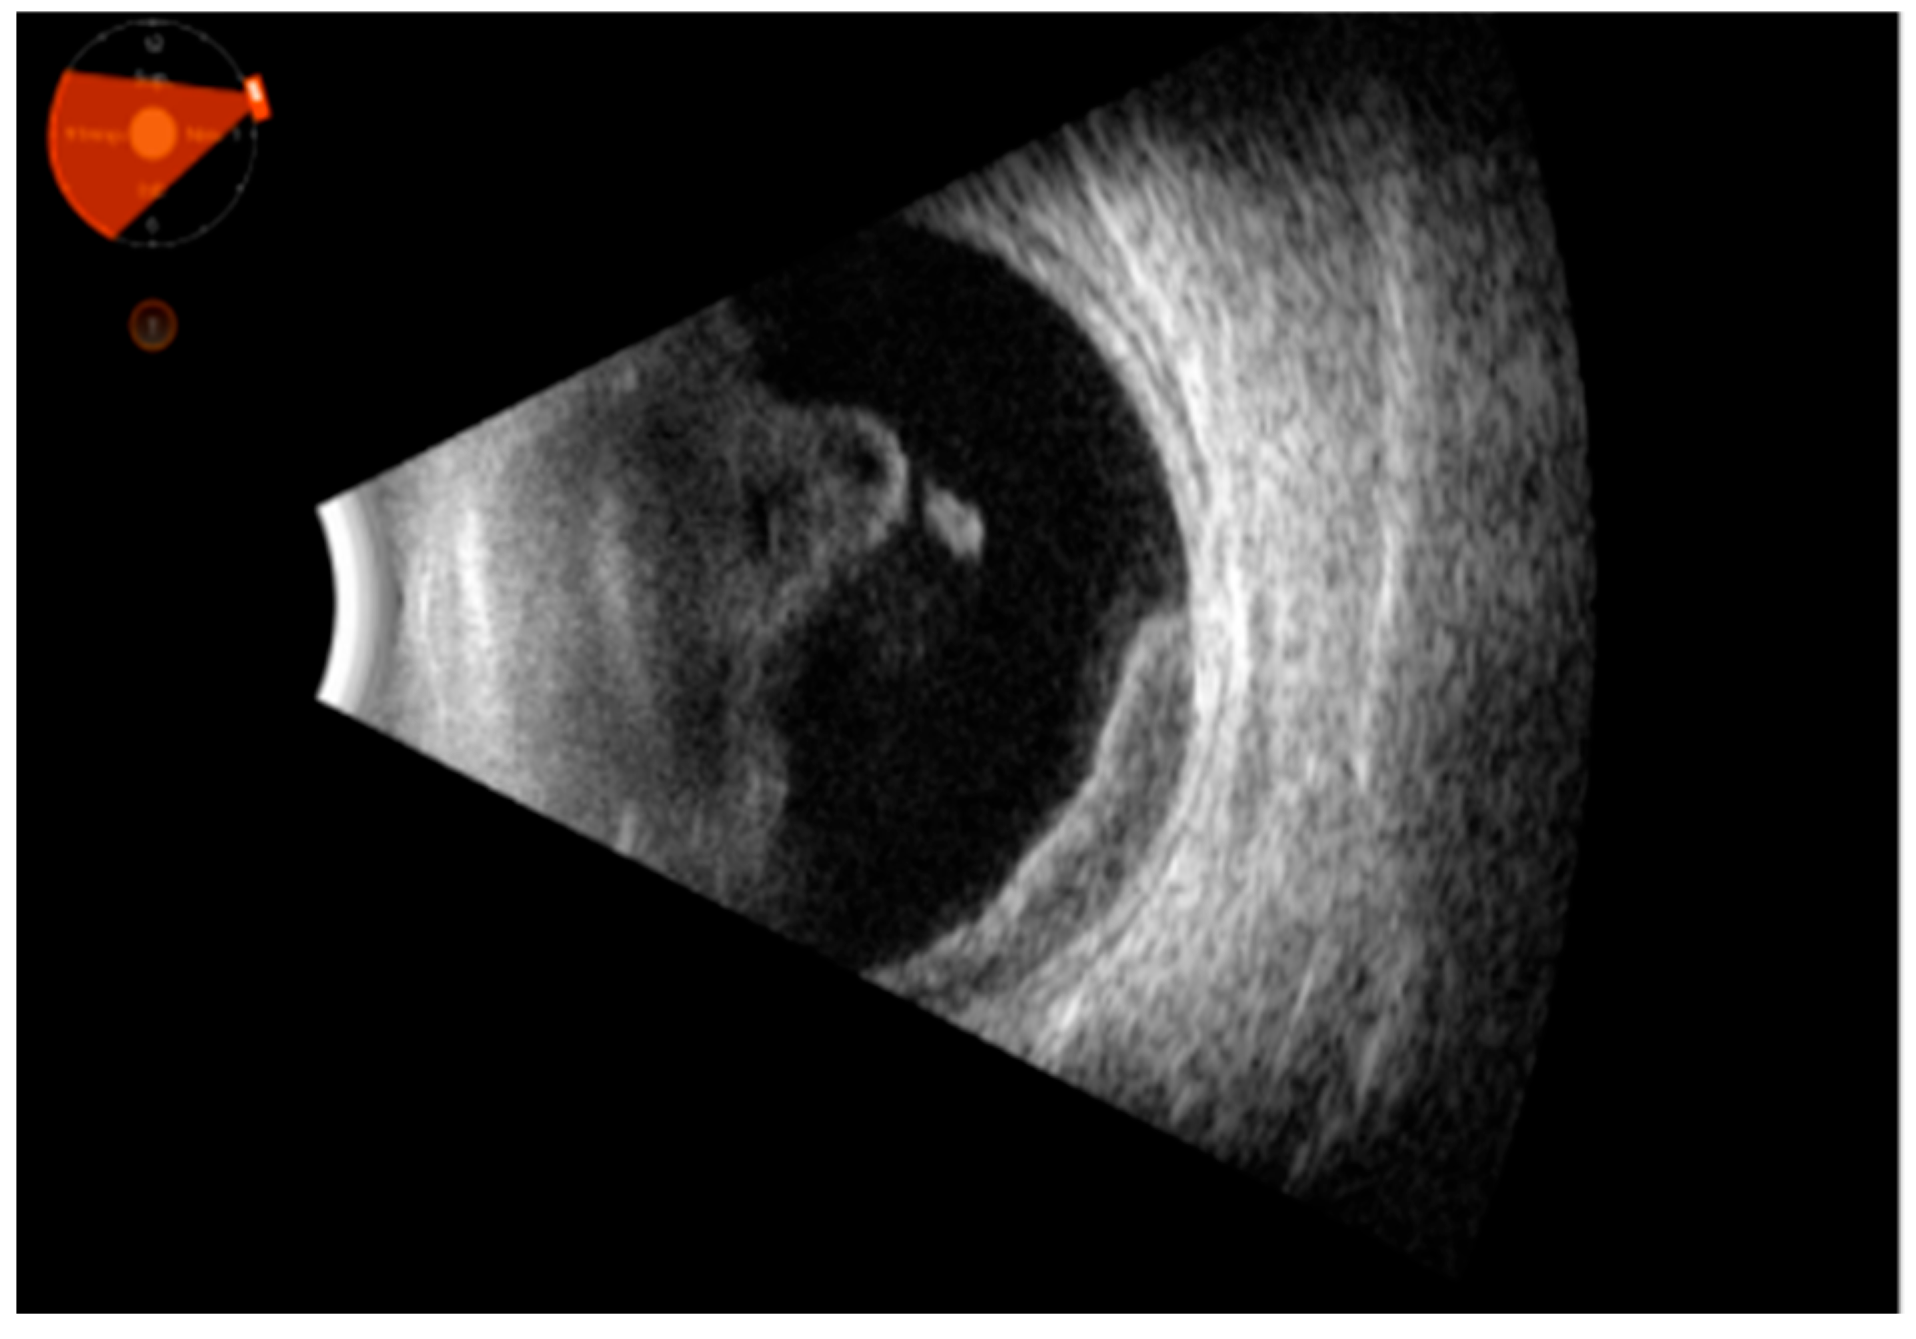

Posterior exudation: This was aligned with the retinal profile with vitreous adherences or organized in the vitreous cavity in single or multiple foci. Among these, we found some forms of intraocular lymphoma or systemic lymphoma, and some bacterial or fungi infections, always associated with vitreous corpuscles.

Corpuscles of the vitreous and/or thickening of the choroid or extrinsic muscles: This formed the common sonographic picture of lymphoma and other lymphoproliferative conditions.

Representative images are given in Figure 1, Figure 2 and Figure 3.

Figure 2. Ultrasound picture of abundant vitreous corpuscles organized into clusters in the anterior vitreous, with high cellularity and mobility. Moreover, the picture shows a highly cellular structure with medium–high reflectivity in the temporal sector, at times in continuity with the vitreous (intraocular lymphoma).